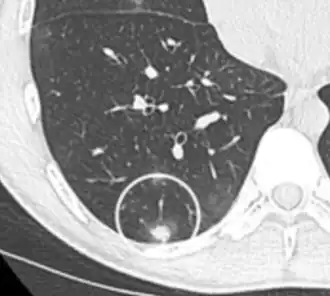

Not every round spot on a radiological image is a solitary pulmonary nodule: it may be confused with the projection of a structure of the chest wall or skin, such as a nipple, a healing rib fracture or electrocardiographic monitoring.

Low attenuating nodule (in this case a fat containing hamartoma).[9] -

Cavitation with relatively thick wall, in this case aspergilloma).[9]